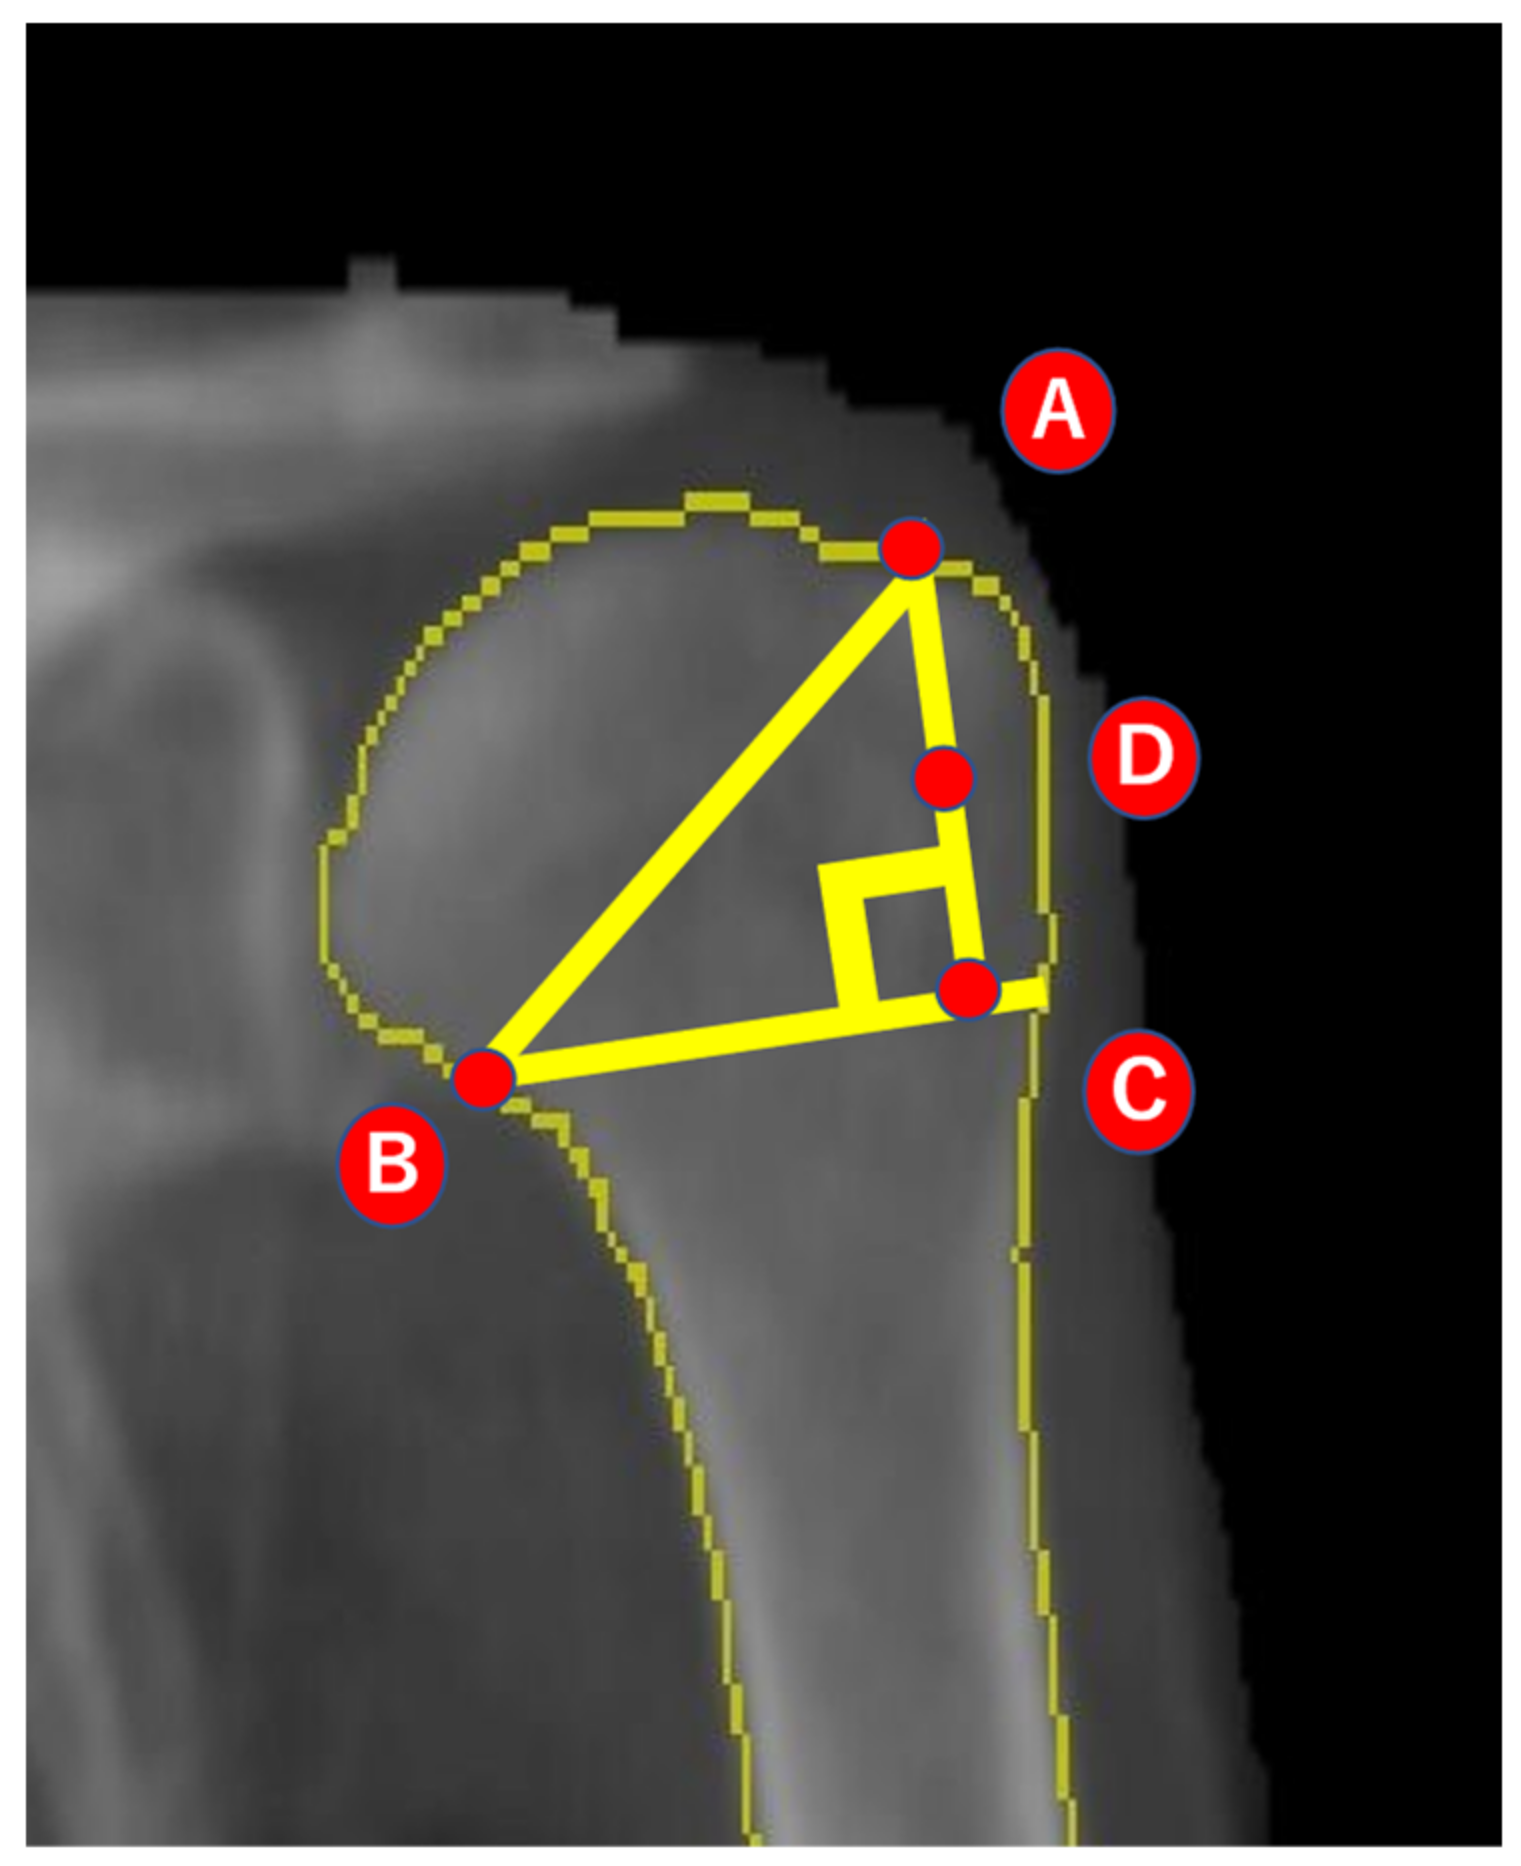

2.2. Analysis of BMD